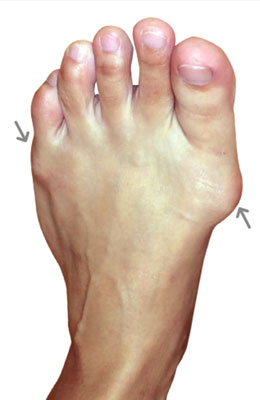

Before

Osteotomy Bunionectomy and Osteotomy Tailors Bunionectomy BEFORE

After

Osteotomy Bunionectomy and Osteotomy Tailors Bunionectomy

Barbara is a 34-year-old working mother of 3 with a painful and somewhat arthritic bunion and tailor’s bunion in her fifth metatarsal. Not only did she have a bunion, but she has hallux rigidus with a stiff great toe and bursitis. We used our osteotomy bunionectomy and osteotomy tailor’s bunionectomy to correct her bunion deformity and also get rid of her forming arthritis. She was able to continue to work and place weight on her foot right after surgery and was back in shoes at 5 weeks post-surgery. Barbara worked throughout her recovery and never missed a beat.

The after picture taken immediately after surgery.